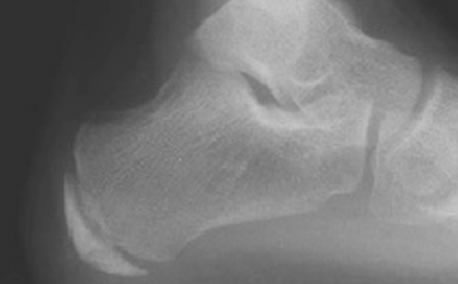

Clinical examination is sufficient to diagnose heel pain attributed to “Severs Disease”. If the symptoms are associated with an altered foot shape such as a flat foot your surgeon would identify this and treat as required. X-Rays can be taken but are not always indicated.